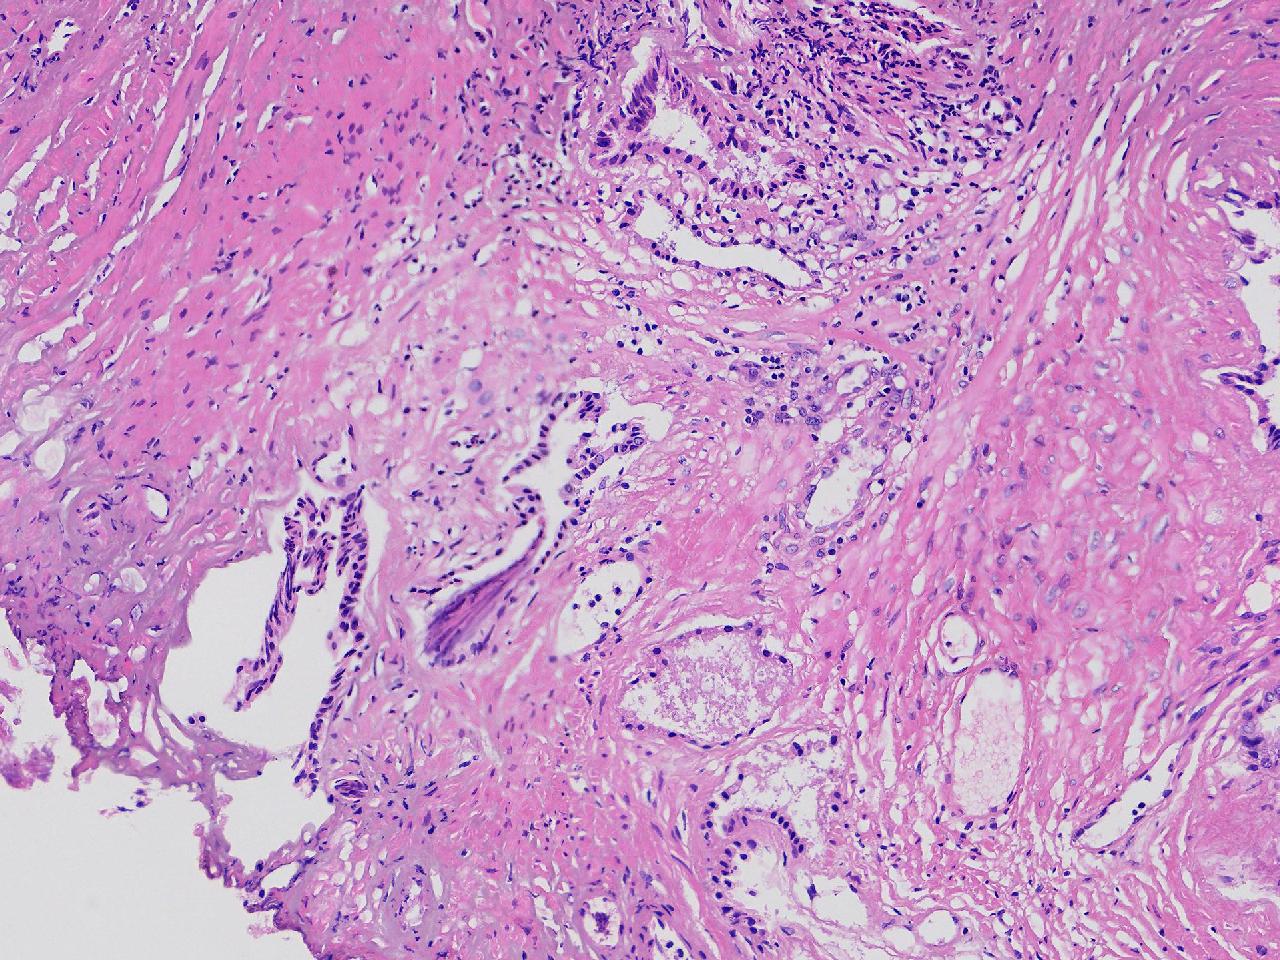

这些腺体有问题吗?

男,77岁,排尿困难2年,尿潴留3天。

标本名称

电切前列腺组织

条索状软组织多块,5X5X4厘米。